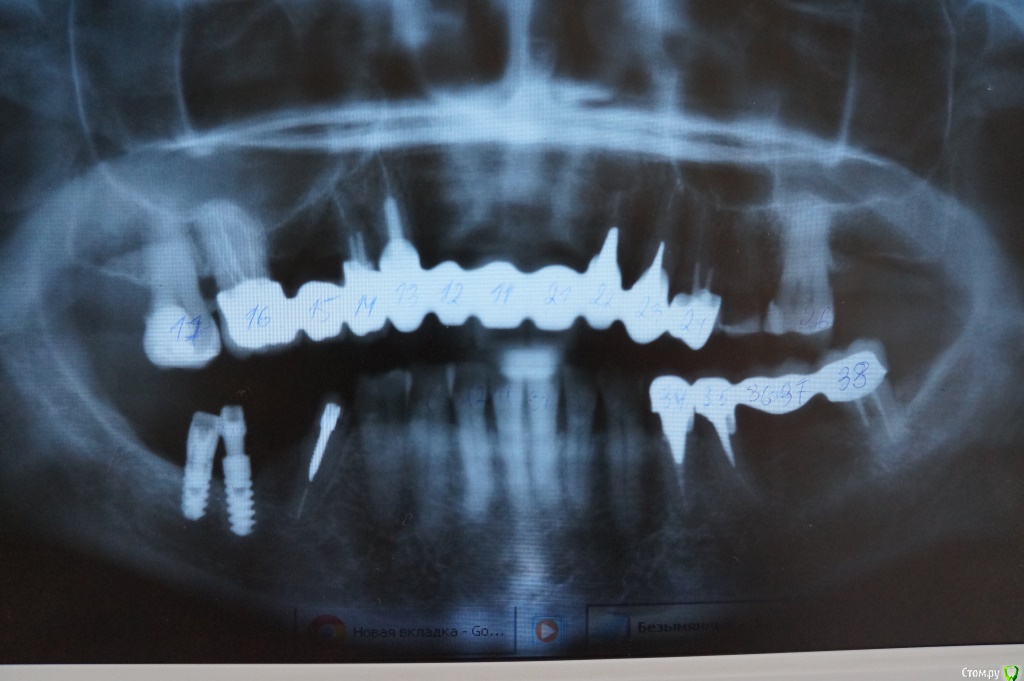

Evitavonni Опубликовано 26 января, 2015 Поделиться Опубликовано 26 января, 2015 Уважаемые доктора стоматологи, необходимо ваше мнение - что делать? Надеюсь, что в прилагаемой панораме что-то можно рассмотреть. В данный момент все металлокерамические конструкции легко снимаются, каждый день дважды снимаю, чищу и фиксирую на 16 и 24 верхний, на 38-й нижний на крем корегу. 46-й имплант выпал. Вкладки все рассосались, короче, ситуация ужасная. Почти решилась на базальную имплантацию, но почитав отзывы на форуме, поняла, что не всему можно верить насчет чудес, о которых пишут о них на некоторых сайтах клиник. Действительно ли, что это чистый бизнес без гарантии и не стоит рисковать своим здоровьем? Можно ли обойтись без синус-лифтинга и подсадки кости при двухэтапной имплантации? Ссылка на комментарий

Evitavonni Опубликовано 29 января, 2015 Автор Поделиться Опубликовано 29 января, 2015 Не той стороной выложили снимок Уважаемый доктор! Снимок переложила. Подскажите пожалуйста, что в моем случае более оптимально на верхней челюсти - "all on four" или все-таки двухэтапная имплантация, которая наверно, потребует синус-лифтинга? Очень привлекает первое - короткие сроки, стоимость.На нижней без пластики тоже не обойтись? Каково Ваше мнение? Спасибо. Ссылка на комментарий

Alejandro Опубликовано 30 января, 2015 Поделиться Опубликовано 30 января, 2015 Нужны прицельные снимки, на ОПТГ не очень чётко видно. Возможно, несколько зубов удасться сохранить. Ссылка на комментарий